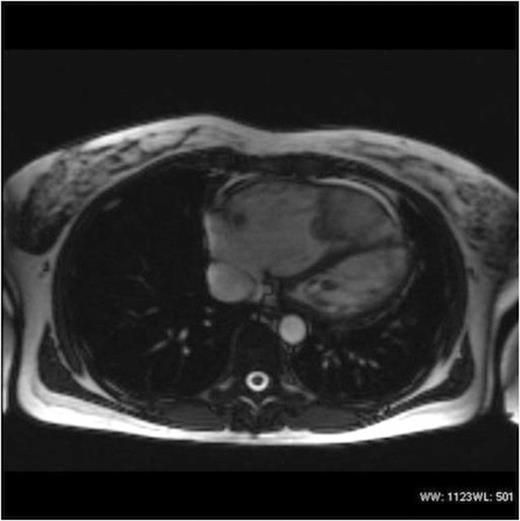

Echocardiography revealed a very large lobulated heterogenous mass in the right ventricular apex. A further mass or extension of this was also seen in the right ventricular outflow tract. This extension was mobile and had a homogenous texture. MRI and CT Thorax (Figures 1 & 2) demonstrated a 4.1cm x 9cm x 4.1cm lobulated mass within the right ventricle, obstructing the right ventricular outflow tract.

The patient made a full recovery and discharged 5 days after surgery. Histology confirmed complete excision of a myxoma. (Figure 3)